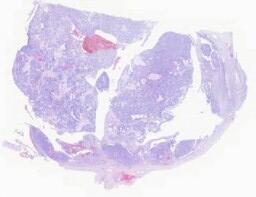

临床资料: 男性,69岁,体检发现右侧肾上腺肿物3年入院。CT示:右侧肾上腺区见大小约48×42mm类圆形囊实性团块灶,形态规则,增强扫描病变边缘的实性部分有明显强化,囊性部分未见明显强化;高血压病史3+年。术中所见:右侧肾上腺可见大小约4.0×3.5cm圆形新生物,与周围组织粘连,术中血压明显波动,最高220/90毫米汞柱,切除肿瘤送检。

大体所见: 包块一个,5×4×2.5cm,已剖开,切面呈囊实性,囊性区3×3×1.8cm,囊内容物已流失,囊壁较光滑,实性区切面灰黄,质中。